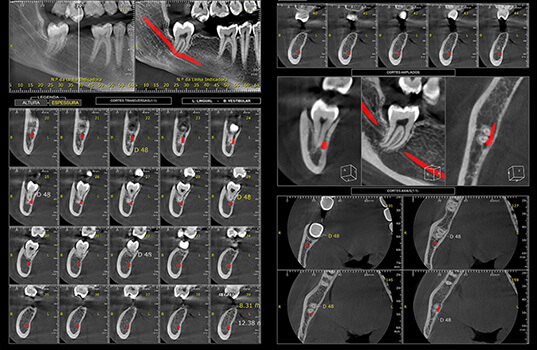

A Tomografia Computadorizada Cone Beam é uma radiografia 3D que é bastante usada na odontologia para ter uma visão detalhada dos ossos da boca, mandíbula e maxila. Ela é muito útil para descobrir problemas como fraturas, tumores, cistos, infecções e outros problemas dentários. Além disso, a Tomografia Computadorizada Cone Beam também é usada para planejar cirurgias na boca, como a colocação de implantes dentários, como também para avaliar o desenvolvimento de tratamentos.

Na Tomografia Computadorizada Cone Beam, o paciente é posicionado na máquina de Raio-X, que gira ao redor da cabeça para fazer uma série de imagens 3D. Em seguida, um profissional especializado utilizando um software junta as imagens para formar uma visão detalhada das estruturas ósseas da boca.

Em resumo, a Tomografia Computadorizada Cone Beam é uma ferramenta valiosa na odontologia, no qual permite aos dentistas terem uma visão detalhada das estruturas ósseas da boca para diagnosticar e tratar problemas de saúde.